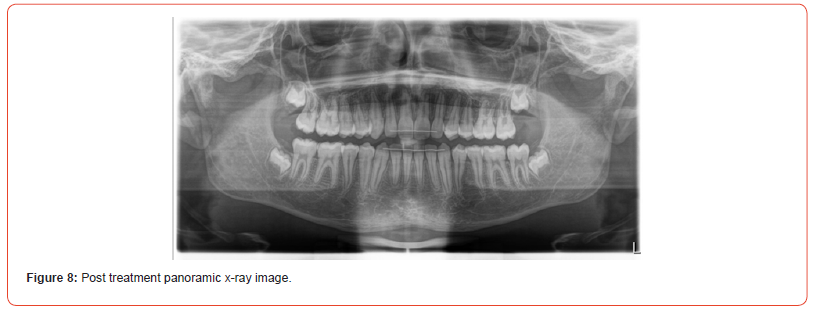

The case was finished with the canines and molars on the righthand side in class I relationship. The left maxillary first premolar was adjusted with composite to resemble a canine and finished in class I occlusion good gingival zenith, and the molar on the lefthand side in a full unit class II (Figure 6). The case was finished with a balanced, functional occlusion and favorable facial aesthetics (Figure 7).